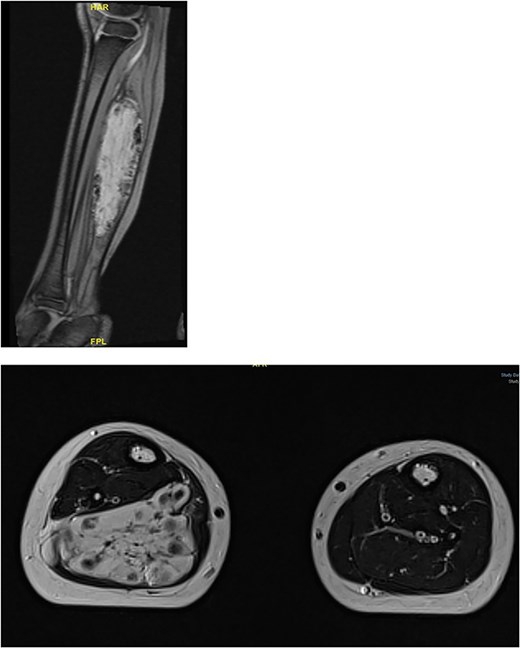

Physical examination revealed a tip-toe gait with a fixed 35° right ankle equinus deformity (Fig. 1). A firm, non-tender swelling measuring 7 × 3 cm was observed in the posterior mid-leg. Asymmetric leg circumferences were noted (right: 22 cm, left: 20 cm), along with a 1 cm leg length discrepancy, which was confirmed radiologically. Radiographic imaging of the right leg showed a posterior soft tissue shadow with areas of ectopic calcification. Contrast-enhanced MRI revealed a large, lobulated soft tissue lesion measuring 5 × 2.8 × 10 cm, located deep within the calf muscles (Fig. 2). The lesion contained multiple calcified phleboliths and exhibited an isointense signal on T1-weighted images with high signal intensity on T2-weighted images, consistent with an IMH.

Large, lobulated intramuscular soft tissue vascular lesion with multiple calcified phleboliths, suggesting intramuscular hemangioma.